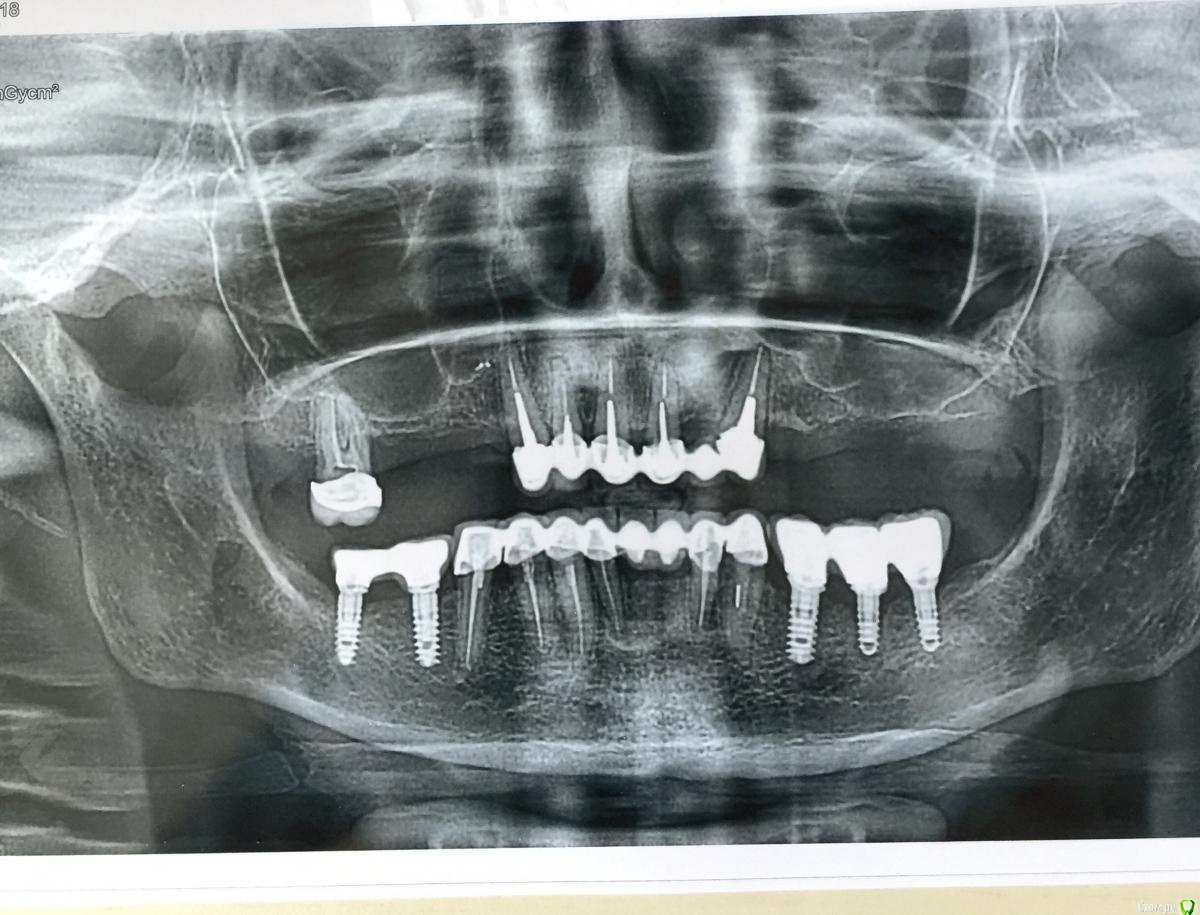

Mars12 Опубликовано 13 марта, 2018 Поделиться Опубликовано 13 марта, 2018 Доброго дня, уважаемые доктора!Были установлены имплантаты, протезирование было в декабре, после протезирования начала воспаляться десна,( где три имплантата) при попадание пищи с кислотой (фрукты, кисломолочные продукты) щиплет и пульсация при физ.нагрузке.Врач на снимках ничего не видит, но факт на лицо, фото прилагается!В чём причина воспаление десны?Да, и выскажитесь по поводы прикреплённой десны, точнее её нехваткой со стороны трёх имплантов!Заранее благодарю! Ссылка на комментарий

Irouil Опубликовано 13 марта, 2018 Поделиться Опубликовано 13 марта, 2018 Судя по Вашему фото, десны (прикреплённой) и вправду маловато. Но Ваши жалобы могут быть связаны и с рядом стоящими зубами. Тут я бы подробнее исследовал их, в первую очередь, и провел десневую пластику вокруг имплантатов (только бы томограмму посмотреть сначала, чтобы убедиться, что этого хватит). Ссылка на комментарий

Irouil Опубликовано 13 марта, 2018 Поделиться Опубликовано 13 марта, 2018 Чтобы решать чего хватит а чего нет надо найти причину жалоб. Пока мы ее не знаем что-то заявлять было бы недальновидно Пятый - это какой? Они у Вас все примерно в одинаковом состоянии по снимку Ссылка на комментарий

Mars12 Опубликовано 14 марта, 2018 Автор Поделиться Опубликовано 14 марта, 2018 Доброго дня!Помогите разобраться ( обозначила на снимке)Верхний зуб беспокоит, при кусании чувствуется тупая боль(как будто штифт давит на корень)Нижние три имплантата, смущает кость(точнее её нехватка ) Простите за такие вопросы,объём работы большой и деньги немаленькие, ещё нужно делать верхнюю челюсть, поэтому задаю вопросы , доктор на них не может ответить... Ссылка на комментарий

Irouil Опубликовано 14 марта, 2018 Поделиться Опубликовано 14 марта, 2018 Спасибо!С Днём рождения Вас!Здоровья, успехов и всего самого наилучшего!Пятый-это средний, где три имплантата!Спасибо Может быть формируется карман, но тут надо во рту смотреть: по снимкам точно сказать я не смогу. Верхний зуб выглядит нормально, но если беспокоит есть смысл сделать КТ. Возможно что-то панорамный снимок недоговаривает. Ссылка на комментарий